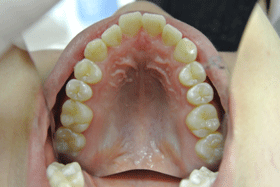

一度も虫歯になってない口腔内

症 例